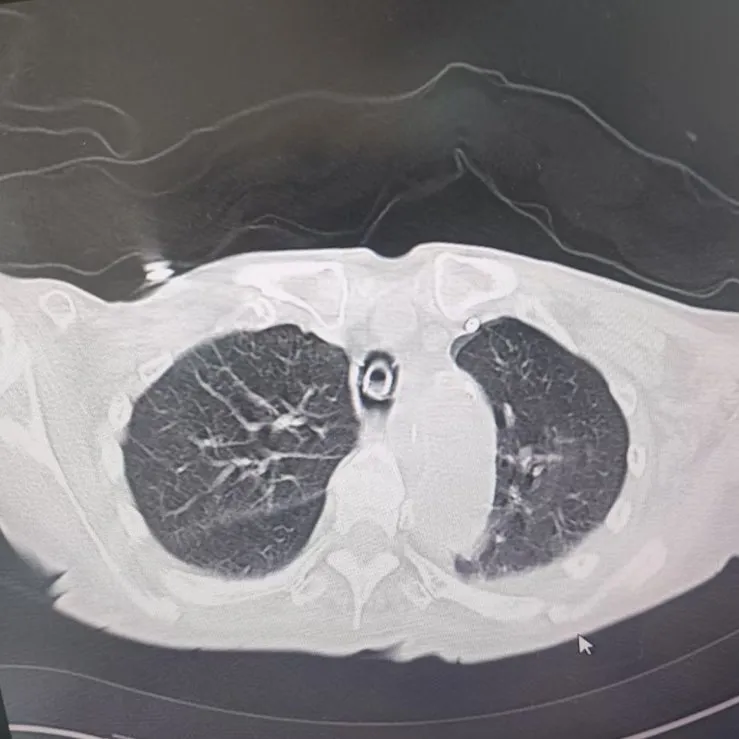

引言 / / Introduction 年近8旬的陳阿姨(化名)因腦梗長(zhǎng)期癱瘓?jiān)诖?,康?fù)期間突然高燒不退,體溫升至39℃,在抗感染過(guò)程中,她并發(fā)高滲性脫水,病情急劇惡化,被緊急送入ICU。此時(shí),她已氣管切開(kāi),依靠呼吸機(jī)維持呼吸,并伴有低蛋白血癥、低鉀高鈉血癥及房顫等多種危重情況,命懸一線! PART. 01 多重泛耐藥菌疊加大量基礎(chǔ)病 治療陷入“死胡同” 呼吸與危重癥醫(yī)學(xué)科及ICU通力協(xié)作,穩(wěn)住患者生命體征。治療過(guò)程中,進(jìn)一步的病原學(xué)檢查結(jié)果令人心驚:陳阿姨的肺部遭遇多種“超級(jí)細(xì)菌”混合侵襲,包括銅綠假單胞菌、鮑曼不動(dòng)桿菌、嗜麥芽窄食單胞菌、金黃色葡萄球菌、木糖氧化無(wú)色桿菌、粘質(zhì)沙雷菌等高度耐藥菌,堪稱(chēng)耐藥菌“大本營(yíng)”。這些細(xì)菌對(duì)常用抗生素幾乎全部耐藥,治療難度高,死亡率高。 治療前患者肺部影像 PART. 02 多學(xué)科強(qiáng)強(qiáng)聯(lián)手 量身定制攻堅(jiān)方案 面對(duì)無(wú)藥可用的困境,呼吸科沒(méi)有放棄!宋剛主任帶領(lǐng)團(tuán)隊(duì)聯(lián)合藥學(xué)部、檢驗(yàn)科、重癥醫(yī)學(xué)科成立多學(xué)科治療組,根據(jù)患者身體情況實(shí)時(shí)調(diào)整用藥,逐一攻破耐藥菌。這場(chǎng)與“超級(jí)細(xì)菌”的拉鋸戰(zhàn)持續(xù)了30多個(gè)日夜。 在醫(yī)護(hù)日夜堅(jiān)守和家屬全力配合下,陳阿姨的感染終于被遏制:高燒退了,肺部陰影消散了!就在即將宣告勝利時(shí),又發(fā)現(xiàn)她存在泌尿感染問(wèn)題,隨即轉(zhuǎn)入泌尿外科協(xié)同治療。當(dāng)宋主任回訪時(shí),看到陳阿姨精神煥發(fā)、體溫平穩(wěn),所有參與救治的人都感慨萬(wàn)分!這場(chǎng)救治,正是呼吸與危重癥醫(yī)學(xué)科攻堅(jiān)耐藥菌硬實(shí)力的生動(dòng)體現(xiàn)! 治療后患者肺部影像 從“無(wú)藥可用”到“絕處逢生”,此次成功救治,集中體現(xiàn)了呼吸與危重癥醫(yī)學(xué)科以耐藥菌精準(zhǔn)診治為核心的學(xué)科特色與技術(shù)優(yōu)勢(shì)。面對(duì)一次次的嚴(yán)峻挑戰(zhàn),科室始終秉持“生命至上、知難而進(jìn)”的信念,以多學(xué)科協(xié)作為平臺(tái),憑借個(gè)體化精準(zhǔn)用藥策略,為患者尋找生機(jī),為更多陷入困境的患者和家庭帶去了實(shí)實(shí)在在的希望。 PART. 03 人民醫(yī)院 人民名醫(yī) 宋剛 主任醫(yī)師 ·葫蘆島市第二人民醫(yī)院呼吸與危重癥醫(yī)學(xué)科主任 ·遼寧省生命科學(xué)學(xué)會(huì)東北呼吸與危重癥醫(yī)學(xué)(PCCM)分會(huì)遼寧省基層委員會(huì)副主任委員 ·遼寧省細(xì)胞生物學(xué)學(xué)會(huì)放射粒子治療專(zhuān)業(yè)委員會(huì)理事 ·遼寧省抗擊新冠肺炎疫情先進(jìn)個(gè)人 ·葫蘆島市勞動(dòng)鑒定委員會(huì)專(zhuān)家?guī)斐蓡T ·葫蘆島市醫(yī)學(xué)會(huì)呼吸內(nèi)科學(xué)分會(huì)第三屆委員會(huì)副主任委員 專(zhuān)業(yè)特色:擅長(zhǎng)呼吸系統(tǒng)疑難及急危重患者的救治,如急慢性支氣管炎、支氣管哮喘、慢性阻塞性肺疾病、肺炎、肺栓塞、肺癌、間質(zhì)性肺疾病、睡眠呼吸暫停綜合征等,尤其擅長(zhǎng)有創(chuàng)無(wú)創(chuàng)機(jī)械通氣、支氣管鏡下相關(guān)檢查及治療(TBNA、氣道支架置入術(shù)、球囊擴(kuò)張等)、全肺灌洗術(shù)等領(lǐng)先技術(shù),發(fā)表國(guó)家級(jí)期刊多篇。